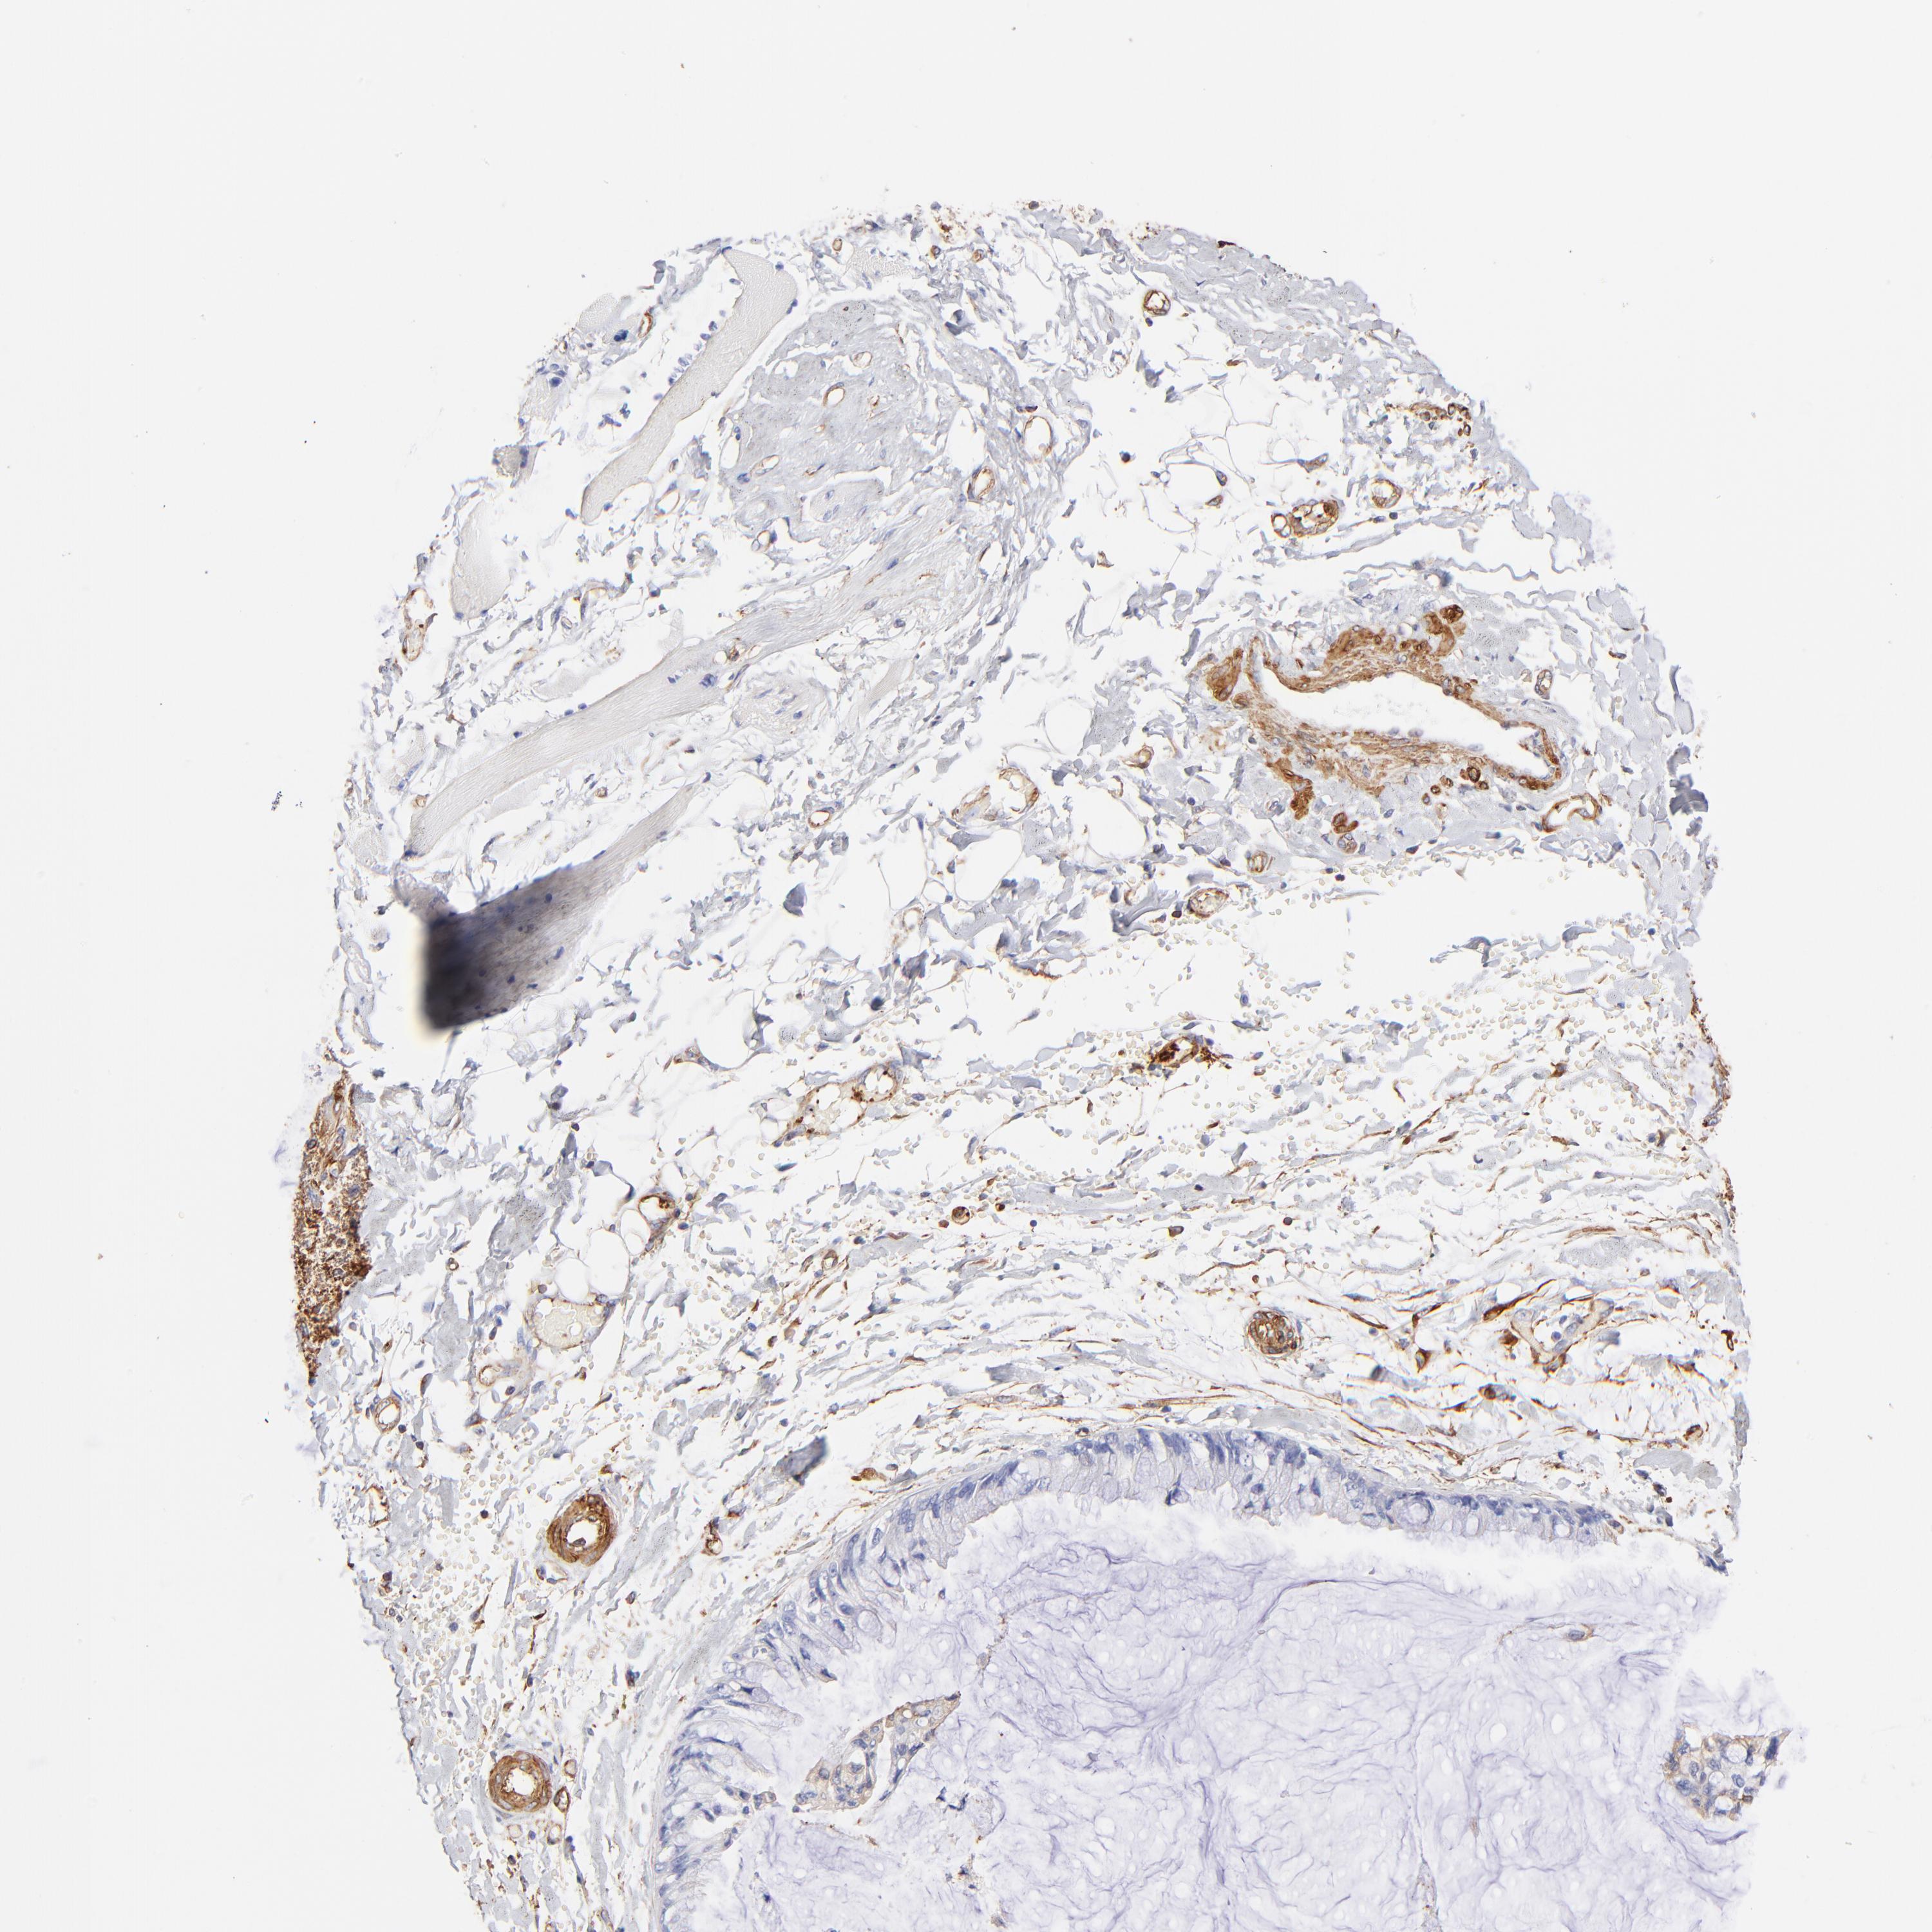

OVARIAN CANCER - Protein expressioni

A mouse-over function shows sample information and annotation data. Click on an image to view it in a full screen mode. Samples can be filtered based on level of antibody staining by selecting one or several of the following categories: high, medium, low and not detected. The assay and annotation is described here.

Note that samples used for immunohistochemistry by the Human Protein Atlas do not correspond to samples in the TCGA dataset.

Antibody stainingi

Antibody staining in the annotated cell types in the current human tissue is reported as not detected, low, medium, or high, based on conventional immunohistochemistry profiling in selected tissues. This score is based on the combination of the staining intensity and fraction of stained cells.

Each image is clickable and will lead to virtual microscopy that enables deeper exploration of all samples and also displays staining intensity scores, fraction scores and subcellular localization as well as patient and tissue information for each sample.

Antibody HPA001115

Antibody HPA002925

Antibody CAB000356

Staining

High

Medium

Low

Not detected

Intensity

Strong

Moderate

Weak

Negative

Quantity

>75%

75%-25%

<25%

None

Location

Nuclear

Cytoplasmic/membranous

Cytoplasmic/membranous,nuclear

Cystadenocarcinoma, mucinous, NOS

Carcinoma, endometroid

Cystadenocarcinoma, serous, NOS